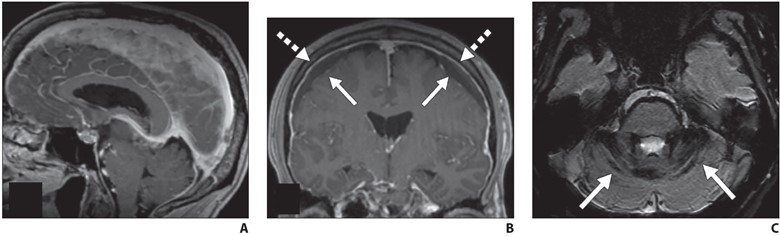

Fig. 1—MRI findings of spontaneous intracranial hypotension.

A, Sagittal contrast-enhanced T1-weighted image shows sagging of brainstem with effacement of mamillopontine, prepontine, and suprasellar intervals as well as engorgement of dural venous sinuses.

B, Coronal contrast-enhanced T1-weighted image shows bilateral subdural hygromas (solid arrows) and diffuse smooth pachymeningeal thickening and enhancement (dashed arrows).

C, Axial susceptibility-weighted image shows diffuse infratentorial hemosiderosis (arrows).